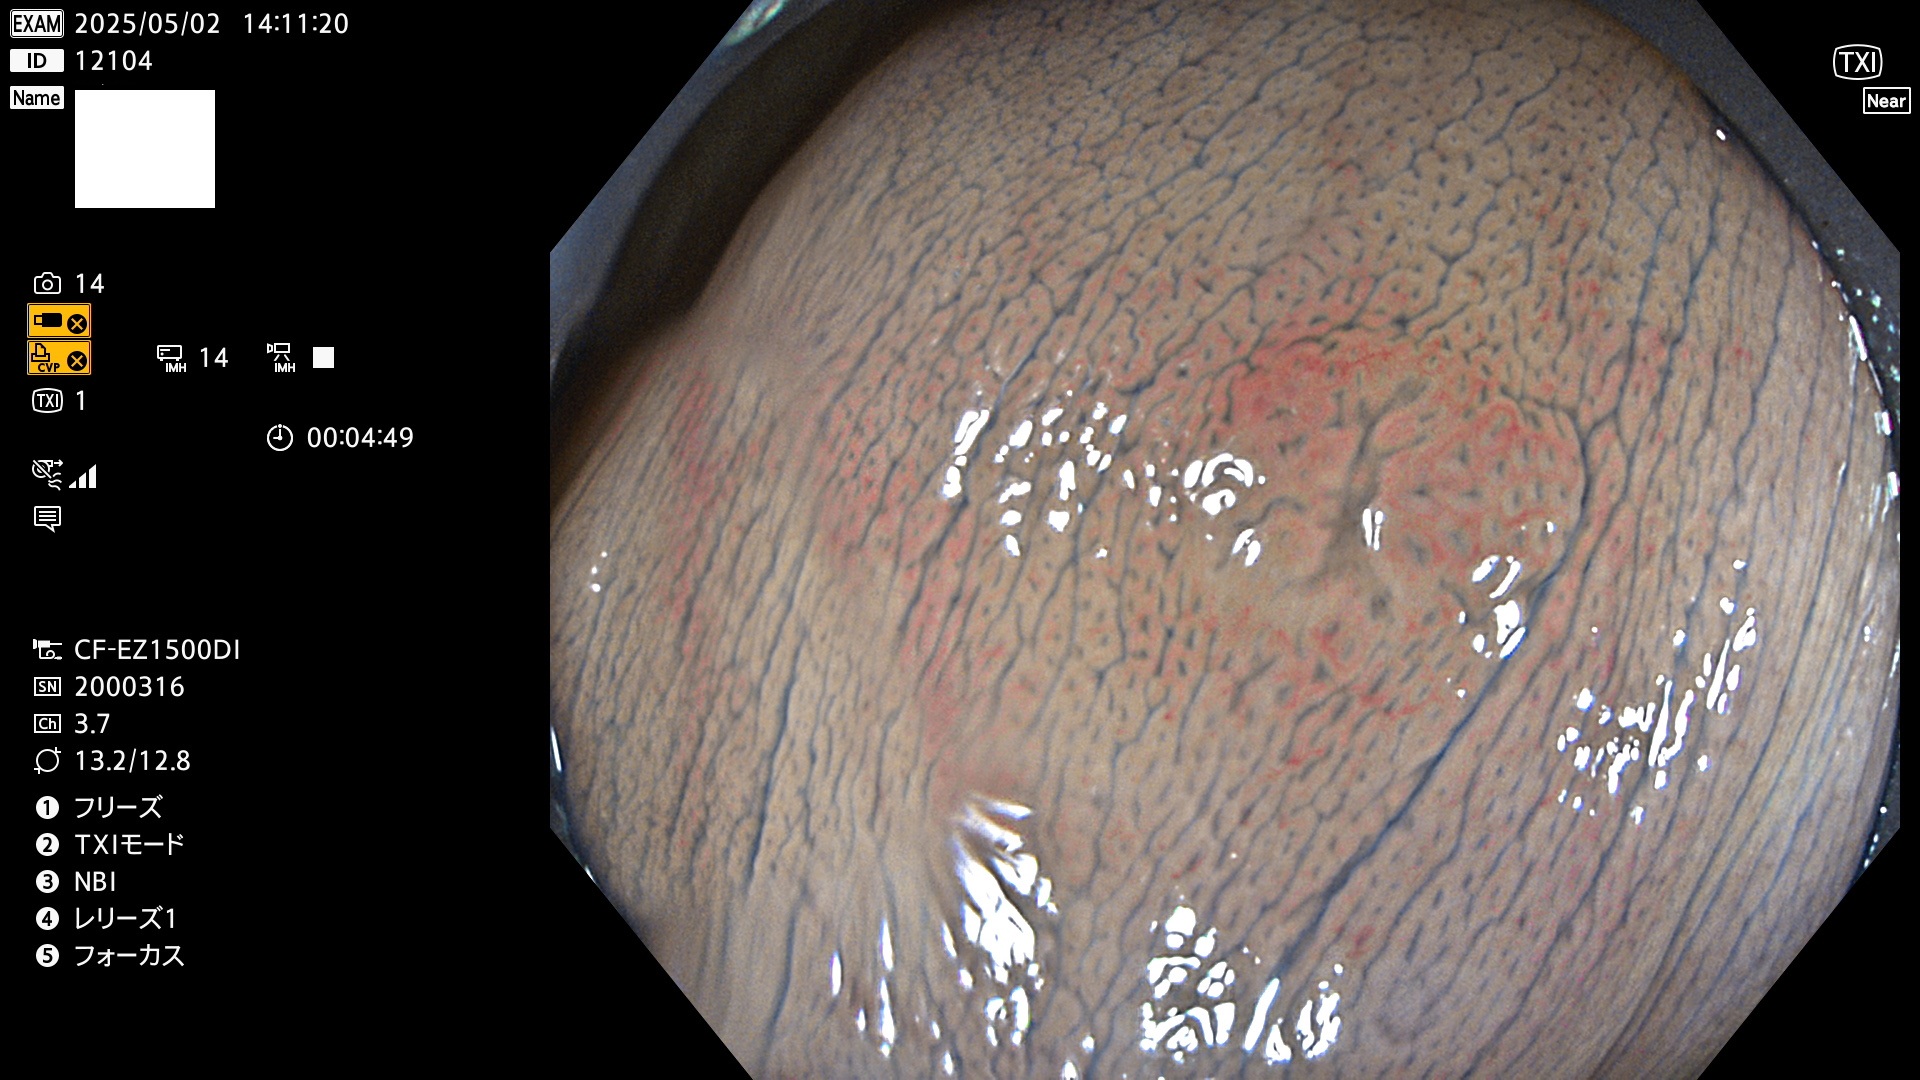

完全に平坦な物をUb、陥凹している物をUcと呼びます。Ubは認識が困難で、Ucはびらん(炎症)と紛らわしいために見落とされやすく、「内視鏡後・大腸癌」の原因になります。

抽出の対象期間 2025年5月1日〜5月2日の2日間(23件の検査)4個 (4/23=17%)